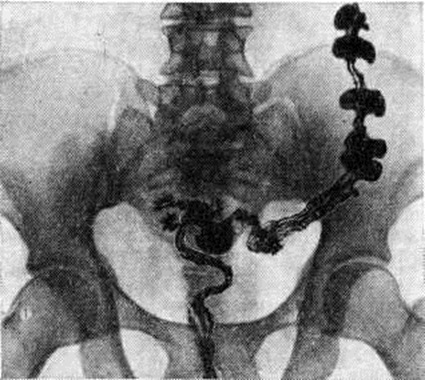

ДиагнозДиагноз устанавливают обычно на основании анамнеза и жалоб больного. Важно выяснение этиологии и типа Запоры, особенно своевременное распознавание опухолевых процессов, вызывающих механический Запоры; при этом наряду с клинический, данными (пожилой возраст, недавнее начало Запоры у лиц с нормальным стулом, примесь крови в кале и другие) большое, диагностическое значение приобретает рентгенологическое исследование, колоноскопия (смотри полный свод знаний), ректор оманоскопия (смотри полный свод знаний). При ректороманоскопии в случае гипермоторики слизистая оболочка прямой и сигмовидной кишок влажная, видна перистальтика, спазмы, окраска слизистой оболочки меняется быстро, при гипомоторике — слизистая оболочка сухая, тусклая, дистальный отдел толстой кишки в спавшемся состоянии, продвижение тубуса затруднено. Известные трудности возникают при дифференциации воспалительных Запоры при колитах и Запоры преимущественно функциональной природы. Распознаванию природы и дифференциации Запоры способствует копрологические исследование (смотри полный свод знаний Кал), биопсия слизистой оболочки прямой или сигмовидной кишки. Большое значение имеет определение типа моторных нарушений толстой кишки. Некоторые данные могут быть получены при пальпации: при преимущественно гипермоторных нарушениях дистальных отделов толстой кишки сигмовидная кишка спастически сокращена, при гипомоторных нарушениях она может быть растянута, не перистальтирует. Важную информацию даёт запись моторики кишечника баллонотензографическим методом. Рентгенологическое исследование имеет целью выявить нарушения моторной функции и тонуса толстой кишки, первичный или вторичный Запоры Его проводят спустя определённые промежутки времени после приёма внутрь бариевой взвеси — через 4— 6—9—12—24—48 часов и позже. Основное внимание обращают на характер заполнения и опорожнения кишки, пассажа по ней бария, вид гаустр, наличие спастических сокращений, а также скоплений газа и жидкости. К ирригоскопии (смотри полный свод знаний) прибегают в случаях, когда необходимо исключить аномалию развития кишки или её органическое поражение, при которых Запоры (вторичный) может быть симптомом заболевания. При первичных Запоры обычно обнаруживают снижение моторной функции, повышение, или понижение тонуса кишки. Эти изменения могут распространяться на всю кишку или на отдельные её сегменты (рисунок 1). Рельеф слизистой оболочки имеет нормальный или несколько «раздражённый» характер (ирритационный рельеф): складки приподняты, расположены более продольно или поперечно, но лишены, признаков воспаления. Смещаемость кишки не нарушена. При гиперкинетических Запоры замедление пассажа бария сочетается с регионарным спазмом и глубокой, нередко сегментирующей гаустрацией в виде многочисленных перетяжек (рисунок 2). Спазмированный отдел кишки иногда имеет вид тонкого шнура (рисунок 3). Реже, при атонических Запоры, обнаруживают пониженный тонус всей толстой кишки или отдельных её сегментов, сопровождающийся расширением просвета, поверхностной сглаженной гаустрацией.